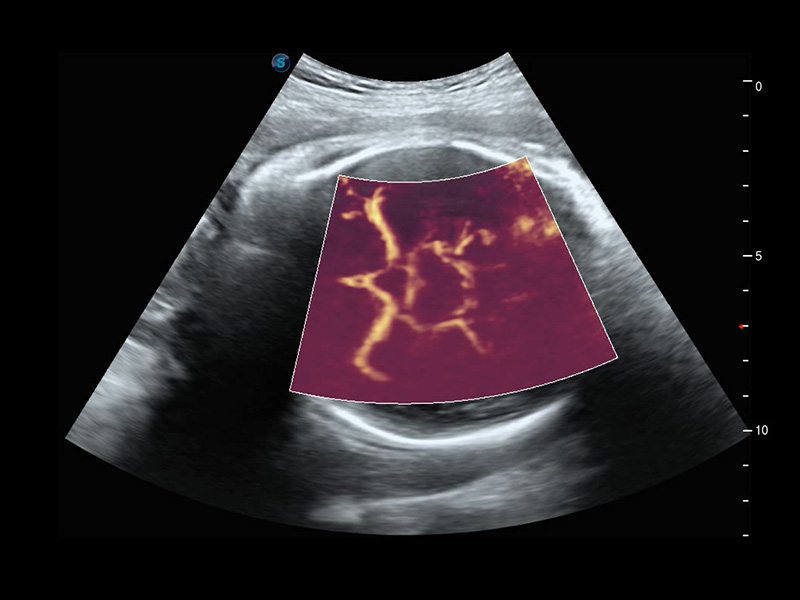

Micro F

Micro F bietet eine innovative Methode, um den sichtbaren Fluss in der Ultraschallbildgebung zu erweitern, insbesondere um den langsamen Fluss kleiner Gefäße sichtbar zu machen. Durch die Verwendung eines fortschrittlichen adaptiven Filters und die Akkumulation von zeitlichen und räumlichen Signalen kann Micro F den geringen Blutfluss effektiv von der Bewegung umgebendem Gewebe unterscheiden und die Hämodynamik mit höherer Empfindlichkeit und räumlicher Auflösung darstellen.

• Zervikales schlecht differenziertes Karzinom mit Micro F

• Fetale Pericallosal-Arterie mit Micro F

• Fetale einseitige Kleinhirnhypoplasie mit Micro F

• Fetaler Leberblutfluss mit Micro F